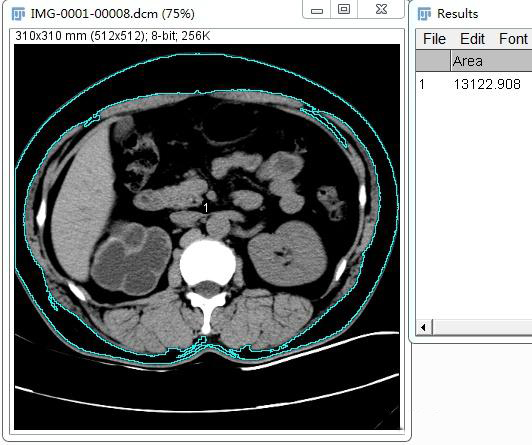

1、魔法棒工具(Wand tool)

利用魔法棒工具(Wand tool)中的图像分割算法,自动识别出区域边界,要求所选区域与周围区域具有明显的界限。

例如可以魔法棒工具勾选皮下脂肪,从而进行面积测量。